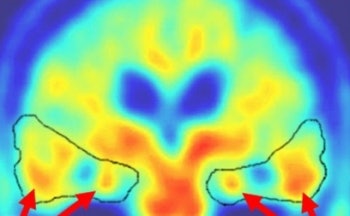

The image demonstrates uptake of the tracer in ß-amyloid senile plaques and neurofibrillary tangles in the brain of an 82-year-old woman with Alzheimer’s disease. These plaques and tangles are the primary characteristic of Alzheimer’s.

Red arrows indicate uptake of FDDNP in the plaques and tangles of the brain that are characteristic of Alzheimer's disease. Image courtesy of Jorge Barrio, PhD |

The name of the tracer is a mouthful: 2-(1-{6-[(2-[18F]fluoroethyl)(methyl) amino]-2-naphthyl}ethylidene)malononitrile, or (18F) FDDNP for short. Wagner believes that FDDNP could prove to be superior to FDG for imaging Alzheimer’s: FDG gives physicians a look at the metabolic activity caused after the onset of the disease, whereas FDDNP measures the actual cause of the pathology years before symptoms occur.

"This is a more direct expression of Alzheimer’s pathology than FDG-PET," Wagner said. "With this tracer, you may be able to get to the pathological process before it actually results in a measurable change in the blood flow."